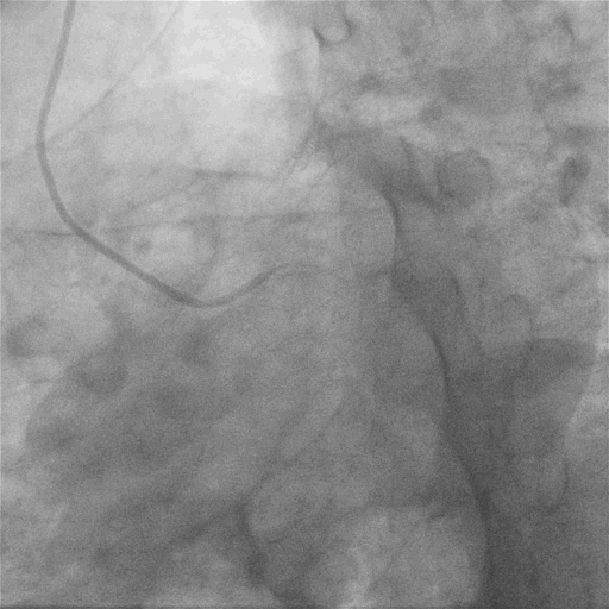

左图:LM未见狭窄及阻塞病变;

右图:LCX未见狭窄及阻塞病变;

左图:LAD近段可见斑块,中段原支架通畅,未见狭窄及阻塞病变;

右图:RCA开口狭窄约50%,近段中段弥漫性斑块,远段后侧支第二转折处局限性狭窄90%;